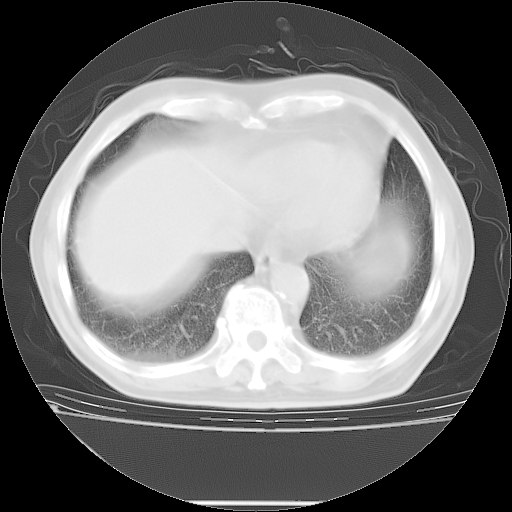

今天复查肺部CT,发现双肺广泛磨玻璃样改变。所以我把3月19日和5月9日相隔50天的肺部CT上传。请大家会诊。

2009年3月19日肺部CT片。

5月9日肺部CT(在4月27日齐鲁医院肺部CT描述部分肺组织磨玻璃样改变,12天后肺组织广泛磨玻璃样改变)

大致读了系列胸部CT:纵隔窗无明显异常,肺窗:从4、27至今:主要是双肺中下野外带可见毛玻璃样改变,目前处于急性肺泡炎阶段,至于原因考虑1、结替组织或胶原血管性疾病所致?2、恶性疾病如恶组在肺部所致的表现或细支气管肺泡癌?3、药物或其它原因如肺蛋白沉着症所致肺泡炎目前不太可能?总之,明天就去请我院的呼吸科、感染科、血液科和临免专家会诊哈。